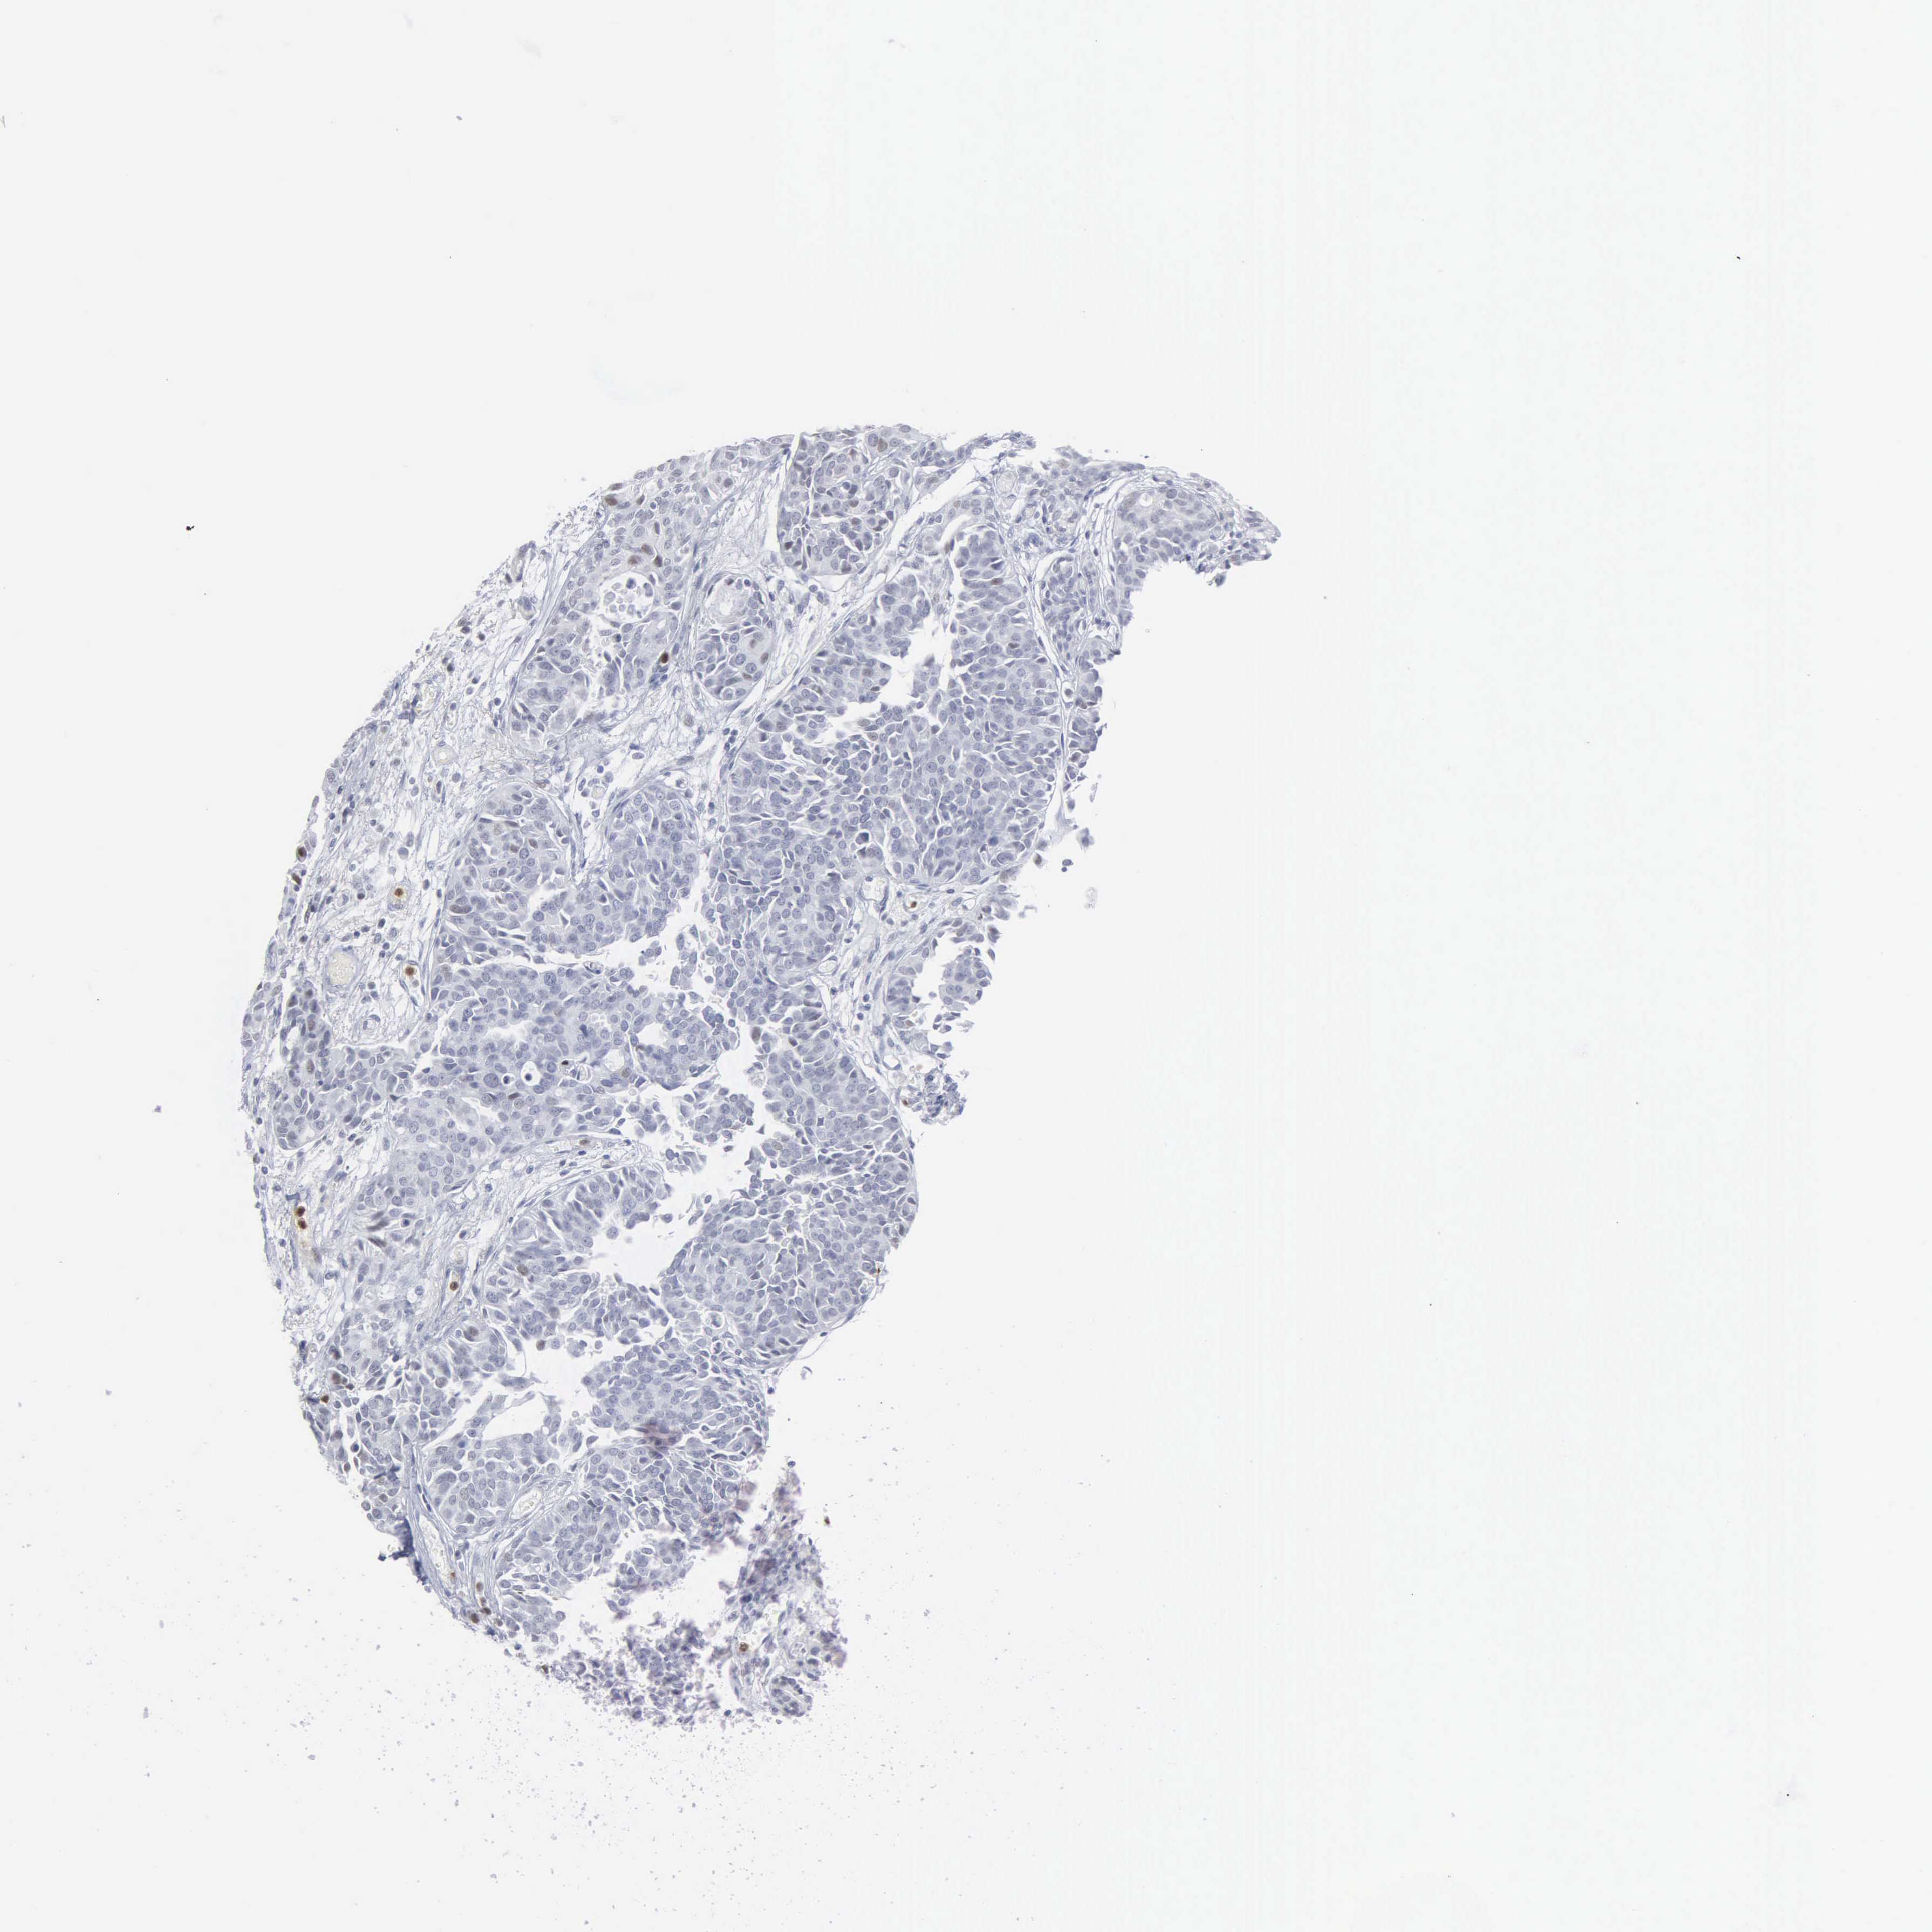

UROTHELIAL CANCER - Protein expressioni

A mouse-over function shows sample information and annotation data. Click on an image to view it in a full screen mode. Samples can be filtered based on level of antibody staining by selecting one or several of the following categories: high, medium, low and not detected. The assay and annotation is described here.

Note that samples used for immunohistochemistry by the Human Protein Atlas do not correspond to samples in the TCGA dataset.

Antibody stainingi

Antibody staining in the annotated cell types in the current human tissue is reported as not detected, low, medium, or high, based on conventional immunohistochemistry profiling in selected tissues. This score is based on the combination of the staining intensity and fraction of stained cells.

Each image is clickable and will lead to virtual microscopy that enables deeper exploration of all samples and also displays staining intensity scores, fraction scores and subcellular localization as well as patient and tissue information for each sample.

Antibody HPA000727

Staining

High

Medium

Low

Not detected

Intensity

Strong

Moderate

Weak

Negative

Quantity

>75%

75%-25%

<25%

None

Location

Nuclear

Cytoplasmic/membranous

Cytoplasmic/membranous,nuclear

Urothelial carcinoma, High grade

Urothelial carcinoma, Low grade